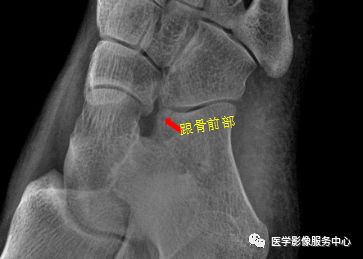

右足斜位示 右侧跟骨前部见骨折透亮线。右跟骨前部骨折。